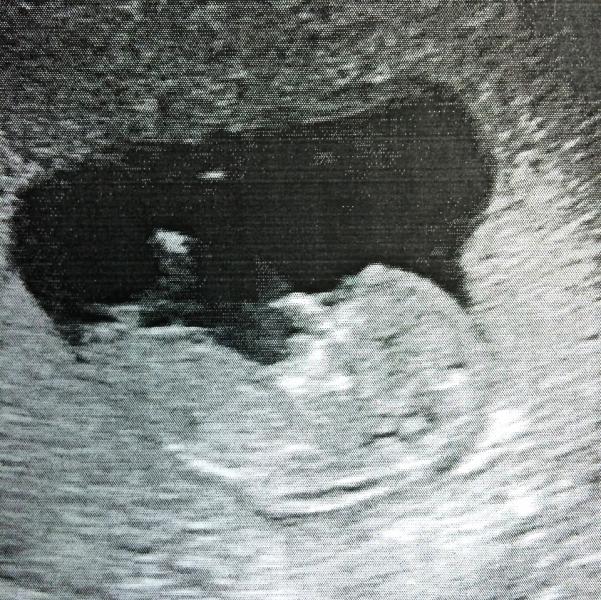

@timonina88 - Кто где?🙈Ничего не понимаю😵Можете закидать меня палками )))

@timonina88 - Ребеночек где?))Я не видела никогда снимков)Вот такой я лох)

@yanarodionova - я на 5 недели смотрела и мы были 2см)))